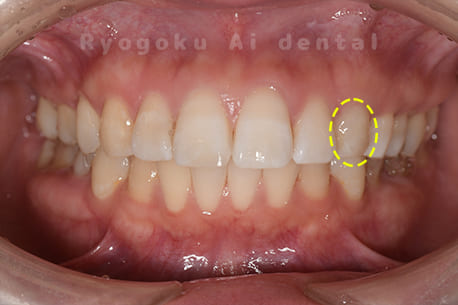

Case03

- 原因

- 失活による歯牙変色

- 治療内容

- ブリーチング+マイクロエンド+ダイレクトボンディング

- 治療費用

- 198,000円(ブリーチング55,000円+マイクロエンド77,000円+ダイレクトボンディング66,000円)

前歯が黒いのが気になるとのことでご来院された患者様です。根の状態も悪かったためマイクロスコープ下で根管治療を行い、ブリーチングの後にダイレクトボンディングで形態修正を行いました。